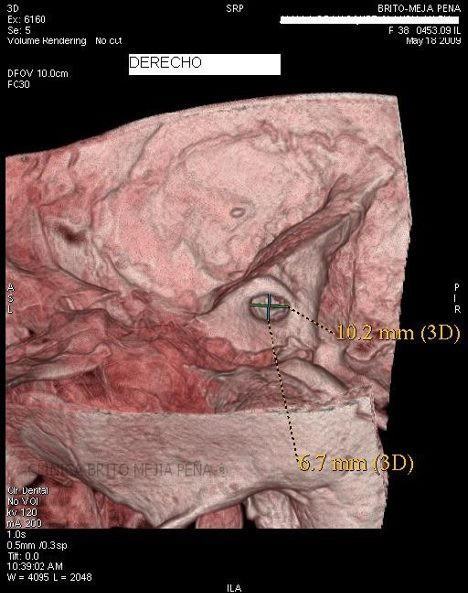

Cabeza y Cuello 2

Envíado por BMP Imágenes Diagnósticas

BMP Imágenes Diagnósticas